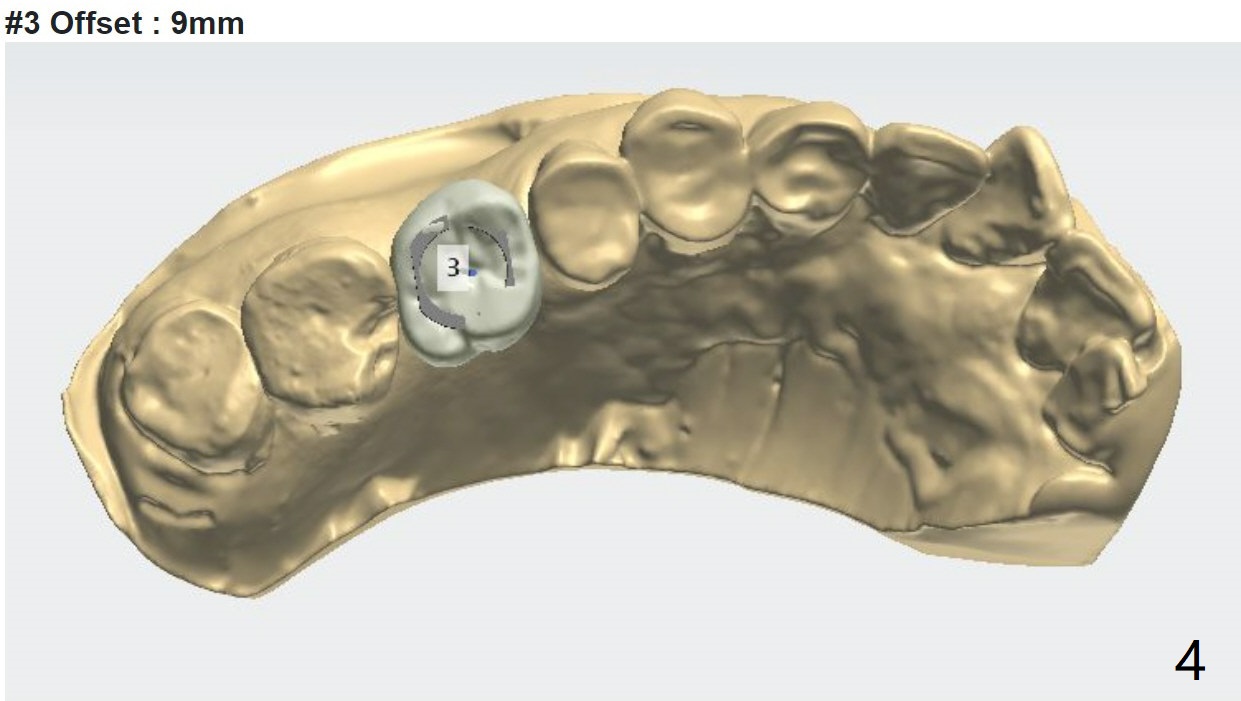

Underdrill for Sinus

A 81-year-old woman

Xin Wei, DDS, PhD, MS 1st edition 06/18/2021, last revision 07/13/2021